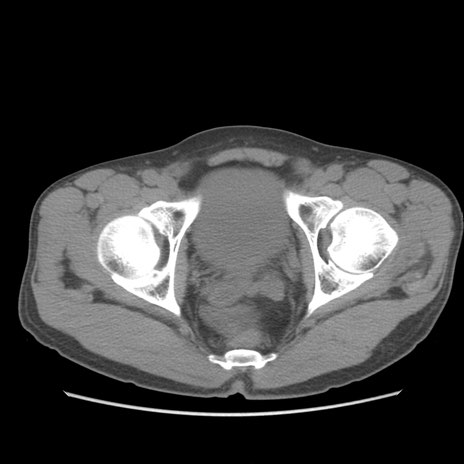

症例56 CT(横断像)

脂肪ウインドウ